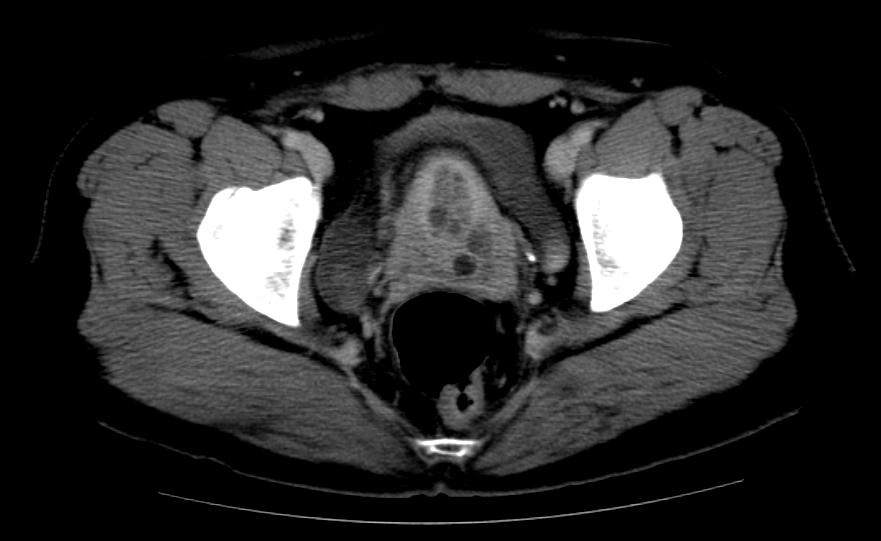

U xơ tử cung ở cổ tử cung (Leiomyoma of the uterine cervix)

16/03/2026